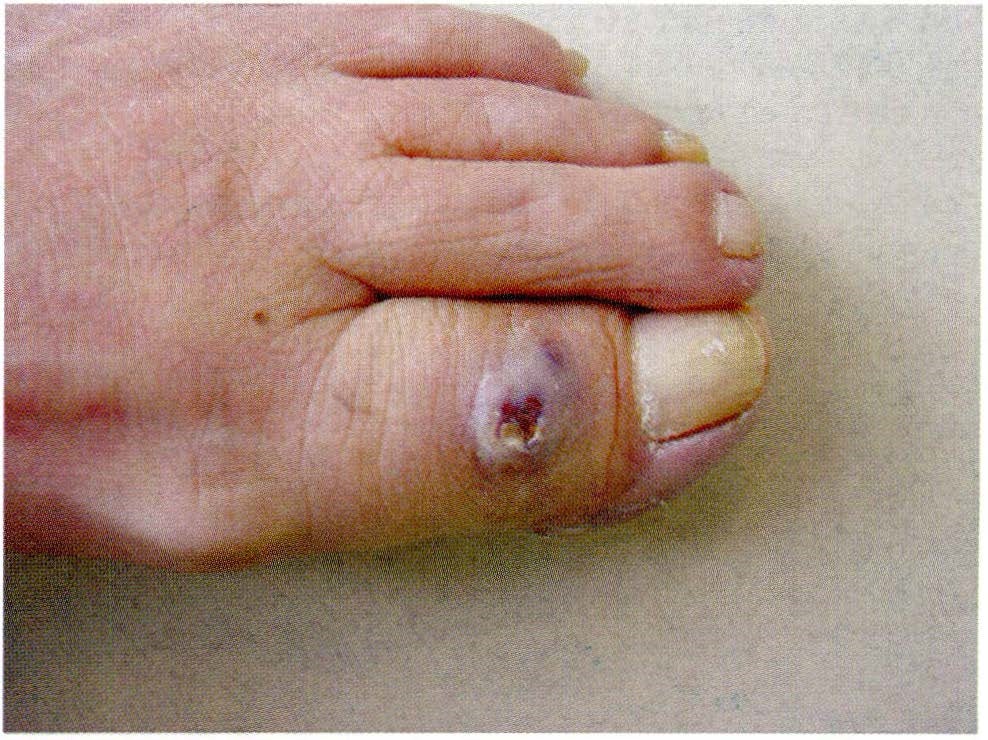

Se presenta el caso de una paciente de sexo femenino, de 70 años de edad, quien consultó por presentar una lesión de un año de evolución en el dorso del primer artejo del pie derecho. Se realiza diagnóstico histopatológico de porocarcinoma. Se reseca la lesión y se corrige el defecto.

El porocarcinoma es una neoplasia poco frecuente, generalmente localizada en los miembros inferiores.